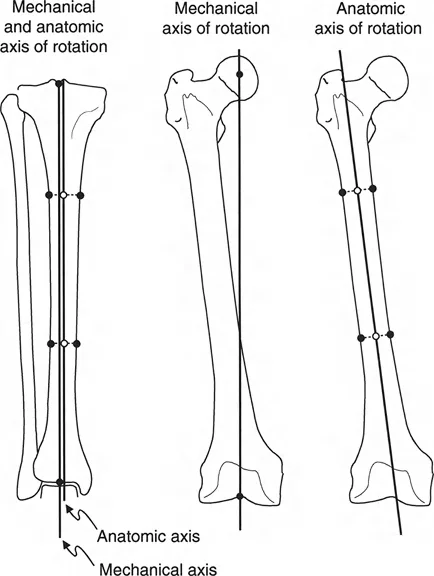

على عكس تشوهات الانحراف الزاوي التي تكون واضحة في الأشعة السينية التقليدية، فإن تشوهات الدوران خفية وتتطلب تقنيات تصوير خاصة وتحليلاً هندسياً دقيقاً.

تحليل دوران الفخذ (Femoral Version Calculation)

يتطلب قياس زاوية دوران الفخذ (Femoral Version) صوراً إشعاعية خاصة تُعرف باسم "تحليل المستوى المائل". يحدد هذا التحليل مدى التواء عظم الفخذ حول محوره.

1. وضعية المريض: يتم الحصول على صورتين بالأشعة السينية (AP و Cross-table Lateral) لمفصل الورك مع توجيه صابونة الركبة للأمام تماماً (وضعية "الركبة للأمام").

2. التثبيت: من الضروري عدم تحريك أو تدوير الطرف بين الصورتين. بدلاً من ذلك، يتم تحريك جهاز الأشعة السينية للحصول على الصورة الجانبية.

3. القياس: يتم قياس زوايا محددة على كل صورة، ثم يتم استخدام هذه القياسات لحساب زاوية الدوران الفعلية.

يفضل الدكتور هطيف استخدام الطريقة المثلثية لحساب هذه الزاوية لضمان أعلى دقة ممكنة، خاصة عندما تكون الزوايا كبيرة.

تتم مقارنة الزاوية المحسوبة بالجانب الآخر السليم (إذا وجد) أو بالنطاق الطبيعي المعروف (عادة ما يتراوح بين 5° إلى 20° من النسخة الأمامية).

تحليل دوران قصبة الساق (Tibial Torsion Analysis)

يتبع تحليل دوران قصبة الساق (Tibial Torsion) منطقاً مشابهاً ولكنه يعتمد على معالم تشريحية مختلفة (الكاحلين). يحدد هذا التحليل مدى التواء عظم قصبة الساق.

1. بروتوكول التصوير: يتم الحصول على صورتين بالأشعة السينية (AP و Lateral) للكاحل مع توجيه صابونة الركبة للأمام.

2. القياس: يتم قياس المسافة العرضية بين الكاحل الإنسي والوحشي على كلتا الصورتين.

3. الرسم البياني: يتم رسم هذه القيم على رسم بياني للمستوى المائل لتحديد اتجاه مستوى الكاحلين.

4. المقارنة: تُقارن زاوية الدوران المحسوبة بالجانب الآخر السليم أو بالنطاق الفسيولوجي الطبيعي (عادة 15° ± 5° من الدوران الخارجي).

تحديد مستوى التشوه بدقة

إن تحديد المستوى الدقيق للتشوه الدوراني هو أحد أهم الخطوات في التخطيط الجراحي. على الرغم من أن الدوران هو تشوه زاوي في المستوى المستعرض، إلا أن موقعه على طول العظم (قريب من المفصل أو بعيد عنه) يؤثر بشكل كبير على كيفية تصحيحه وتأثيره على الأنسجة المحيطة.

- في حالات ما بعد الإصابة: يكون مستوى التشوه واضحاً عادة عند موقع الكسر الملتئم.

- في الحالات الخلقية أو التنموية: يتطلب تحديد مستوى التشوه استنتاجاً سريرياً دقيقاً يعتمد على تأثيره العميق على مسار العضلات والأوتار. يعتمد الدكتور هطيف على خبرته الواسعة في تقييم هذه الحالات لتحديد المستوى الأمثل لقطع العظم.